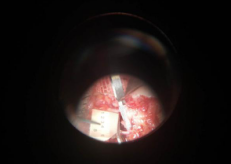

很快完善术前各项检查,接着唐医生手术团队为患者进行了“左手示、中、环指清创示指撕脱皮肤修复+中环指骨折复位内固定血管神经肌腱撕脱皮肤修复甲床术+血管移植术”。术中探查见患者左手中指自甲根部不全离断,仅少许肌腱相连;环指自甲中段完全离断,中指指伸肌腱和指深屈肌自止点近端处部分断裂,中、环指甲床挫裂伤,中、环指远节指骨骨折,示指指端皮肤软组织撕脱。高倍显微镜下探查见左示、中、环指双侧指固有动脉完全断裂伴挫伤,环指双侧指固有神经完全断裂伴挫伤,中指双侧指固有神经部分断裂伴挫伤。术中先手法复位中、环指远节指骨断端,再分别吻接断裂的血管和神经。其中环指血管内径仅0.2毫米,中指血管内径0.3毫米,血管吻接难度相当大。所以,唐医生应用了超级显微外科技术,采用12-0缝合线进行缝合,血管通血良好,手术比较顺利。

术中测量血管内径